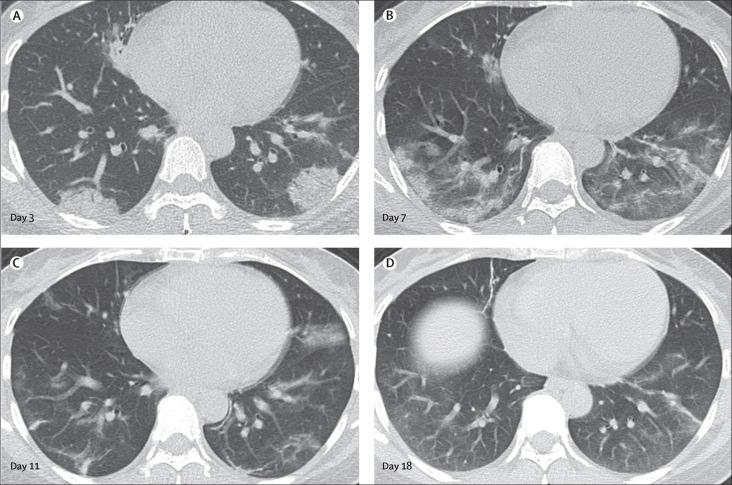

81 patients admitted to hospital between Dec 20, 2019, and Jan 23, 2020, were retrospectively enrolled. The cohort included 42 (52%) men and 39 (48%) women, and the mean age was 49·5 years (SD 11·0). The mean number of involved lung segments was 10·5 (SD 6·4) overall, 2·8 (3·3) in group 1, 11·1 (5·4) in group 2, 13·0 (5·7) in group 3, and 12·1 (5·9) in group 4. The predominant pattern of abnormality observed was bilateral (64 [79%] patients), peripheral (44 [54%]), ill-defined (66 [81%]), and ground-glass opacification (53 [65%]), mainly involving the right lower lobes (225 [27%] of 849 affected segments). In group 1 (n=15), the predominant pattern was unilateral (nine [60%]) and multifocal (eight [53%]) ground-glass opacities (14 [93%]). Lesions quickly evolved to bilateral (19 [90%]), diffuse (11 [52%]) ground-glass opacity predominance (17 [81%]) in group 2 (n=21). Thereafter, the prevalence of ground-glass opacities continued to decrease (17 [57%] of 30 patients in group 3, and five [33%] of 15 in group 4), and consolidation and mixed patterns became more frequent (12 [40%] in group 3, eight [53%] in group 4).

COVID-19 pneumonia manifests with chest CT imaging abnormalities, even in asymptomatic patients, with rapid evolution from focal unilateral to diffuse bilateral ground-glass opacities that progressed to or co-existed with consolidations within 1-3 weeks. Combining assessment of imaging features with clinical and laboratory findings could facilitate early diagnosis of COVID-19 pneumonia.

我们回顾性纳入了 2019 年 12 月 20 日至 2020 年 1 月 23 日期间住院的 81 名患者。该队列包括 42 名(52%)男性和 39 名(48%)女性,平均年龄为 49.5 岁(标准差 11.0)。总体而言,受累肺段数的平均值为 10.5(6.4),组 1 为 2.8(3.3),组 2 为 11.1(5.4),组 3 为 13.0(5.7),组 4 为 12.1(5.9)。观察到的主要异常表现模式为双侧(64 [79%] 例)、外周(44 [54%])、边界不清(66 [81%])和磨玻璃影(53 [65%]),主要累及右下肺叶(225 [27%] 个受累肺段)。在组 1(n=15)中,主要表现为单侧(9 [60%])和多灶性(8 [53%])磨玻璃影(14 [93%])。在组 2(n=21)中,病变迅速发展为双侧(19 [90%])、弥漫性(11 [52%])磨玻璃影为主(17 [81%])。此后,磨玻璃影的患病率继续下降(组 3 中有 30 例患者中的 17 例[57%],组 4 中有 15 例中的 5 例[33%]),实变和混合模式变得更加频繁(组 3 中有 12 例[40%],组 4 中有 8 例[53%])。

COVID-19 肺炎表现为胸部 CT 影像学异常,即使在无症状患者中也是如此,在 1-3 周内从局灶性单侧迅速发展为弥漫性双侧磨玻璃影,并进展或共存实变。结合影像学特征与临床和实验室检查结果进行评估,有助于早期诊断 COVID-19 肺炎。